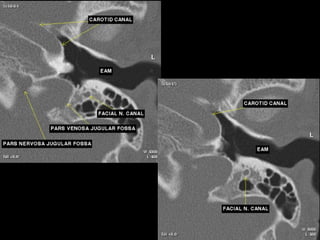

CT Temporal Bone Search Pattern with selected images :

Other structures/landmarks:

•Styloid process

•Stylomastoid foramen

•Petrous apex

•Mastoid air cells

•Sigmoid sinus

•Cochlear promontory

•Carotid canal

•Tegmen

•Jugular bulb

The jugular foramen level

•The jugular foramen – dome shaped outline.

•The mastoid segment of the facial nerve canal can be

identified lateral to the jugular foramen, running nearly

vertical and extending toward the stylomastoid

•foramen.

•The mastoid antrum is seen superiorly and laterally.

•Portions of the lateral and

•superior SCCs can be seen.